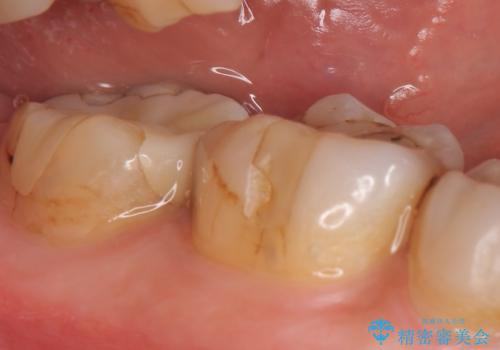

- 昔治療した奥歯の見た目が気になるのでセラミックでやり直したいといらっしゃった方の症例です。

右下6、7の古い詰め物および虫歯を除去後、オールセラミッククラウンによる補綴を行いました。